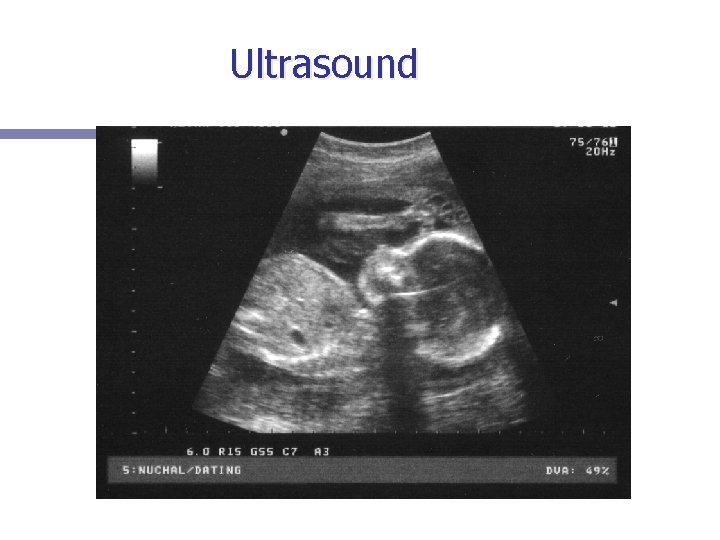

Ultrasound n Definition: Sound or other vibrations having an ultrasonic frequency; particularly as used in medical imaging. Uses high frequency sound waves to generate a moving picture on screen.

Ultrasound